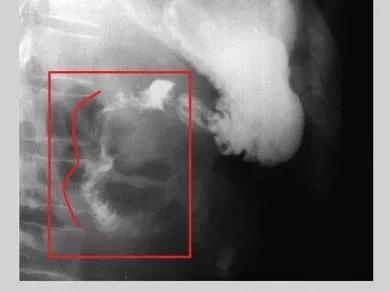

左图上箭头示十二指肠降段内侧小憩室,憩室颈部狭窄,内见气液平面

右图右箭头示意憩室周围肠黏膜皱襞增粗,排空延长,提示憩室炎症

钡餐造影示:十二指肠第二、三段两个向腔外突出的憩室